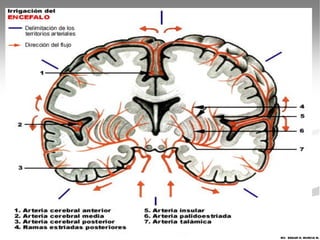

   CIRCULACION SANGUINEA

ENCEFALICA

   Arteria Carótida interna.

   Rama Comunicante Caudal.

   Arteria Cerebral Rostral, Media y Caudal.

   Arteria Basilar.

   Arteria Cerebelar rostral y caudal.

   Arterias Medulares.

VASCULARIZACION DEL ENCEFALO

Esta irrigado por una amplio sistema de ramas

procedente de dos pares de vasos sanguíneos: A.

Carótida Interna y A. Vertebral.

CIRCULACION SANGUINEA ENCEFALICA

A. Arteria Carótida

interna.

B. A. Cerebral Rostral

C. A. Comunicante Caudal.

D. A. Etmoidal interna.

E. A. Meningea rostral.

F. A. Cerebral media.

G. A. Coroidea rostral.

H. A. Cerebral caudal.

j.  A. Cerebelar rostral.

K. A. Cerebelar caudal.

L. A. Basilar cerebral.